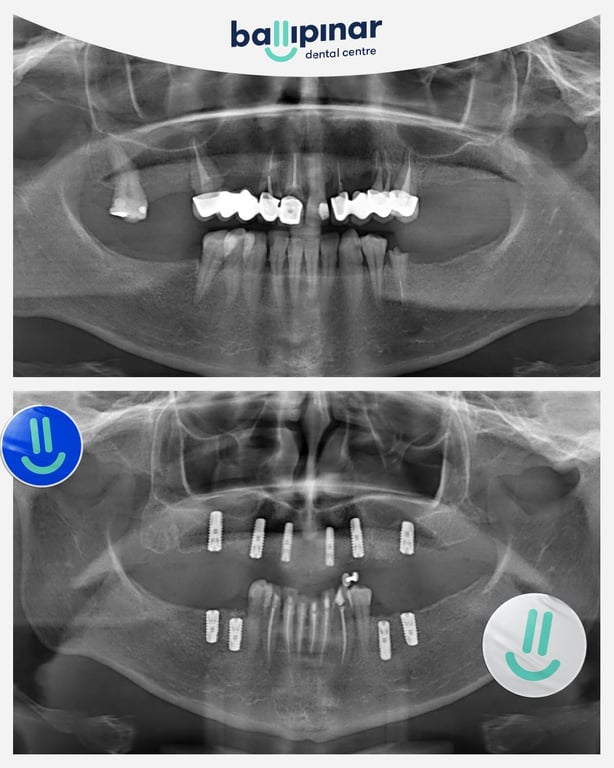

Dental implants Before & After

Explore all the before and after photos of dental implant procedures performed by Ballipinar in Turkey. Contact us today to achieve a beautiful smile.